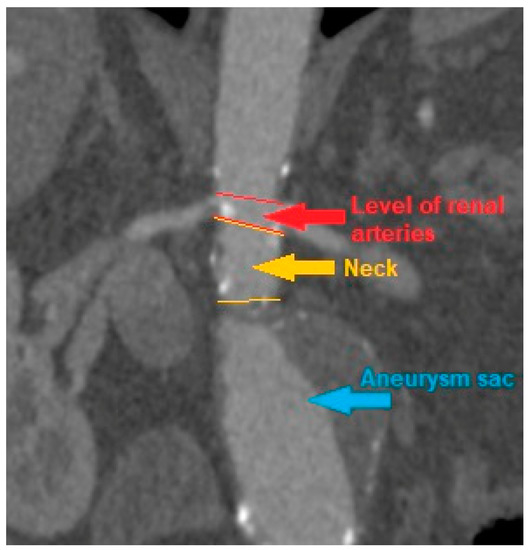

CT scans were analyzed, and the AAA, iliac arteries and aortic diameter were measured at following levels: celiac trunk, superior mesenteric artery, renal arteries, the maximum diameter of the aneurysm sac, understood as the diameter of the AAA at the level with the highest sac circumference, the diameter of both common iliac arteries and both external iliac arteries. In addition, measurements were made of the AAA neck diameter, i.e., the diameter of the aortic section inclined at a right angle to its long axis at the level of the segment above the AAA sac and below the level of the renal arteries, provided that such segment was present at all due to AAA morphology. The diameter was measured between the outer edges of the vessel wall opposite to its center. If ILT was present inside an aneurysm sac it was also included in the measurement of maximal aneurysm diameter. The measurement was made with OsiriX DICOM Viewer program (Figure 1).

Figure 1. An example of computed tomography of patient with infrarenal abdominal aortic aneurysm with present neck segment.